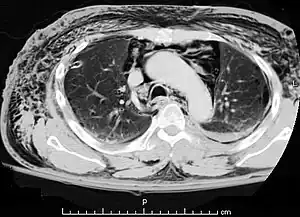

| A CT scan showing air in the mediastinum | |

Pneumomediastinum is uncommon and occurs when air leaks into the mediastinum. The diagnosis can be confirmed via chest X-ray showing a radiolucent outline around the heart and mediastinum or via CT scanning of the thorax.